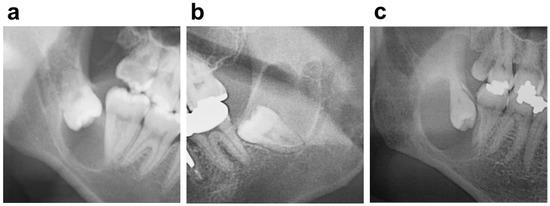

The Clinical features based on the radiolucent area on panoramic radiographs included the site, locular type, and position of the cyst. The locular types were divided into a unilocular type (Figure 1a) and a multilocular type (Figure 1b). The positions of the cysts were divided into a crown side type (the cyst surrounds the crown of the associated third molar) (Figure 1a) and a whole-tooth type (the cyst surrounds the crown and root of the associated third molar) (Figure 1c).

Figure 1.

A dentigerous cyst (a) unilocular and crown side type; (b) multilocular type; (c) whole-tooth type.

There was no bilateral difference in the mandible (left, 52.1%; right, 47.9%). The unilocular (89.1%) in the locular type and the crown side type (68.5%) in the position of the cyst were significant (p-value < 0.05), respectively (Figure 1, Table 1).